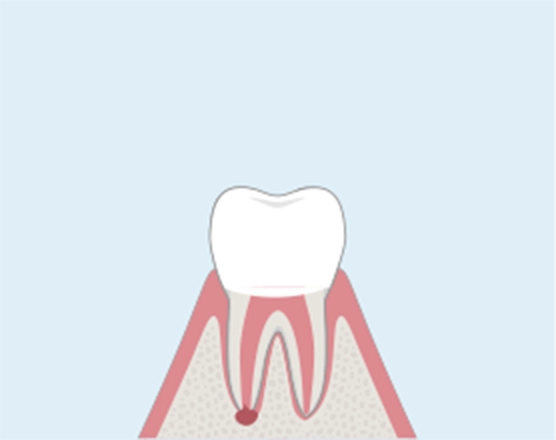

CASE 04

歯根端切除術が難しい場合

意図的再植術

下顎の奥歯や病巣が骨の内側にある場合や、歯の根が割れてしまった場合は、治療対象の歯を一度抜歯し、直接患部を治療した後、再び元の位置に戻す意図的再植術で歯を残せる可能性があります。歯の根は歯根膜という細胞の膜で覆われていて、膜の細胞が死なない限り、一度抜いても高確率で元に戻ります。

01

歯の根の先に膿がたまった状態。

-

02

抜歯して、直接歯の病巣を切除します。

03

病巣部分を除去し、洗浄・殺菌します。

04

歯を元の位置に戻し、歯が固定されるのを待ちます。